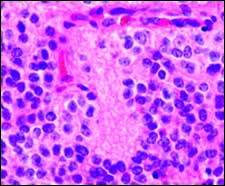

Розетки Флекснера-Винтерштайнера это скопления опухолевых клеток в виде «колеса со спицами» наиболее часто встречающиеся в ретинобластомах и некоторых других опухолях глаза.[2]

В отличие от розеток Гомера Райта центр розетки Флекснера-Винтерштайнера лишен нейропиля с нервными волокнами.[2] Электронная микроскопия показывает, что опухолевые клетки, образующие розетку Флекснера-Винтерштайнера, имеют ультраструктурные особенности примитивных фоторецепторных клеток.[3] Кроме того, просвет розетки имеет те же особенности окрашивания, что и палочки и колбочки[4], из чего можно предположить, что розетки Флекснера-Винтерштайнера представляют собой специфическую форму дифференцировки клеток сетчатки.

Розетки Флекснера-Винтерштейнера не только характерны для ретинобластом, они могут быть обнаружены в пинеалобластомах и медуллоэпителиомах.